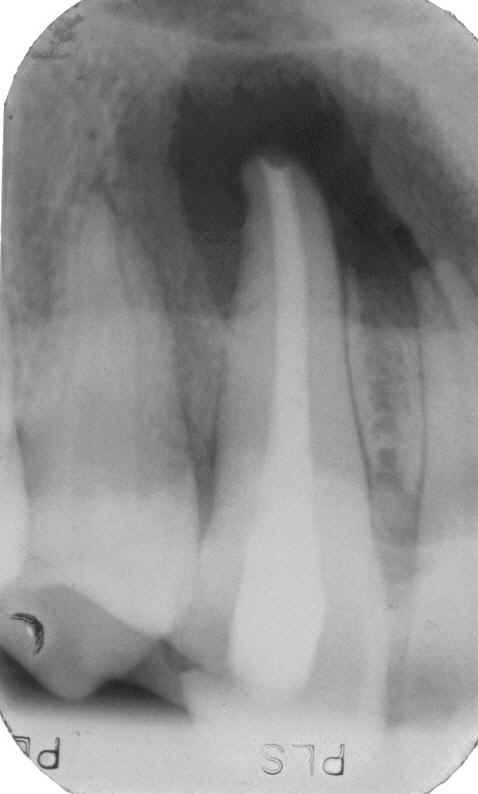

Röntgenologischer Ausgangsbefund

Röntgenologischer Ausgangsbefund im August 1996 bei Zahn 44 mit chronisch apikaler Parodontitis; Zustand vor umfangreicher ZE-Neuversorgung. Erste Therapie der Wahl ist in diesem Fall immer die konventionelle Wurzelkanalbehandlung ohne primär chirurgische Intervention

Wurzelfüllung

Wurzelfüllung im Januar 1997 in lateraler Kondensation mit normierter Guttapercha und AH 26. In der gleichen Sitzung wurde ein Titanstift adhäsiv inseriert mit dessen Hilfe der adhäsive Aufbau des Zahnes erfolgte